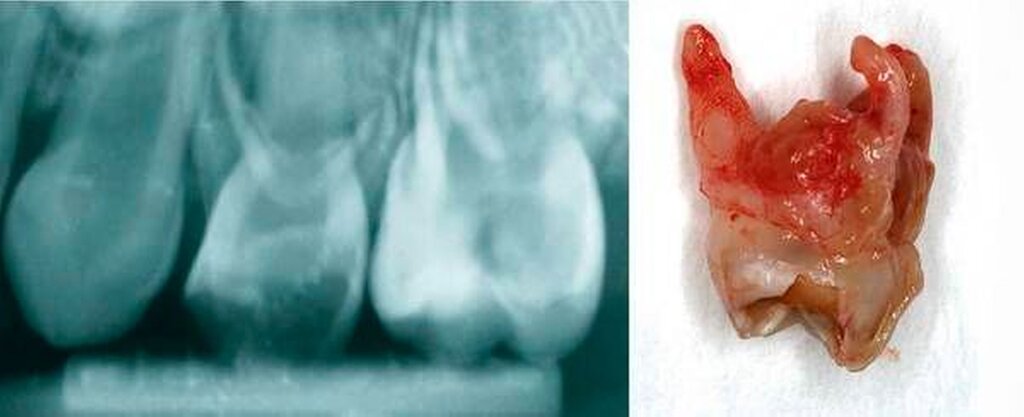

Zentraler Anspruch der Kinderzahnheilkunde ist: Jeder Milchzahn sollte (wenn überhaupt) nur einmal behandelt werden. Daher sind frühzeitige sowie regelmäßige zahnärztliche Kontrollen unerlässlich. Neben einer soliden klinischen Untersuchung (Karies, Zahnfarbe, Schwellung, Rötung, Fistel, Zahnbeweglichkeit in Abhängigkeit von Zahnwechsel, Zustand der Nachbarzähne) spielt die röntgenologische Diagnostik (Umfang der Karies, interradikuläre Aufhellungen, Resorptionen, Lage des Zahnkeims) für die vorausschauende Planung und für die erfolgreiche Therapie eine wichtige Rolle. Vor allem die Röntgenuntersuchung bringt meistens einen entscheidenden Mehrwert, da die Karies bei Kindern aufgrund der breiten, flächigen Approximalkontakte klinisch oft sehr schwer zu diagnostizieren ist (Abbildung 1) [Fuks, 2005].

Auch wenn Eltern sich besorgt in Hinsicht auf die Röntgenstrahlung zeigen, sollte keine Therapie ohne Röntgenbild stattfinden. Nicht selten endet eine scheinbare Fissurenkaries in einer Caries profunda, die mit einer Krone versorgt werden muss. Um sowohl Sicherheit für die Therapieentscheidung zu erlangen als auch die Eltern rechtzeitig über die Intervention aufzuklären, ist das systematische Röntgen bei Kariesverdacht unerlässlich. Bei einer noch nicht kavitierten Läsion am Einzelzahn sollten auch die Zähne des antagonistischen Kiefers mithilfe von Bissflügeln untersucht werden (Abbildung 2).